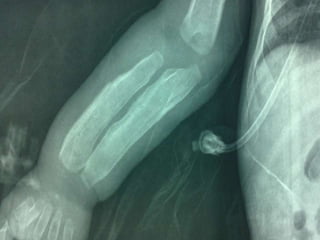

Caffey disease(ICH)AD  .subperiosteal bone formationbefore 6 months, M:f  1:1General hyperirritability, fever and anorexia, painful, firm soft-tissue swelling.PGETTT infants with cyanotic heart disease cortical hyperostosis that mimics ICH. PGE serum levels elevated Indomethacin.

Caffey disease(ICH)AD  .subperiostealbone formationbefore 6 months, M:f 1:1General hyperirritability, fever and anorexia, painful, firm soft-tissue swelling.PGETTT infants with cyanotic heart disease cortical hyperostosis that mimics ICH. PGE serum levels elevated Indomethacin.

DD  - Physiological in infant not more than 4 m.   - trauma.   - Hypervitaminosis A.   - scurvy   - prostaglandin E1 and E2 administration , 42% of infants for more than 30 days; this increases to 100% in more than 60 days.8   - infection (including syphilis)   - metastatic neuroblastoma.

DD -Physiological in infant not more than 4 m. - trauma. - Hypervitaminosis A. - scurvy - prostaglandin E1 and E2 administration , 42% of infants for more than 30 days; this increases to 100% in more than 60 days.8 - infection (including syphilis) - metastatic neuroblastoma.